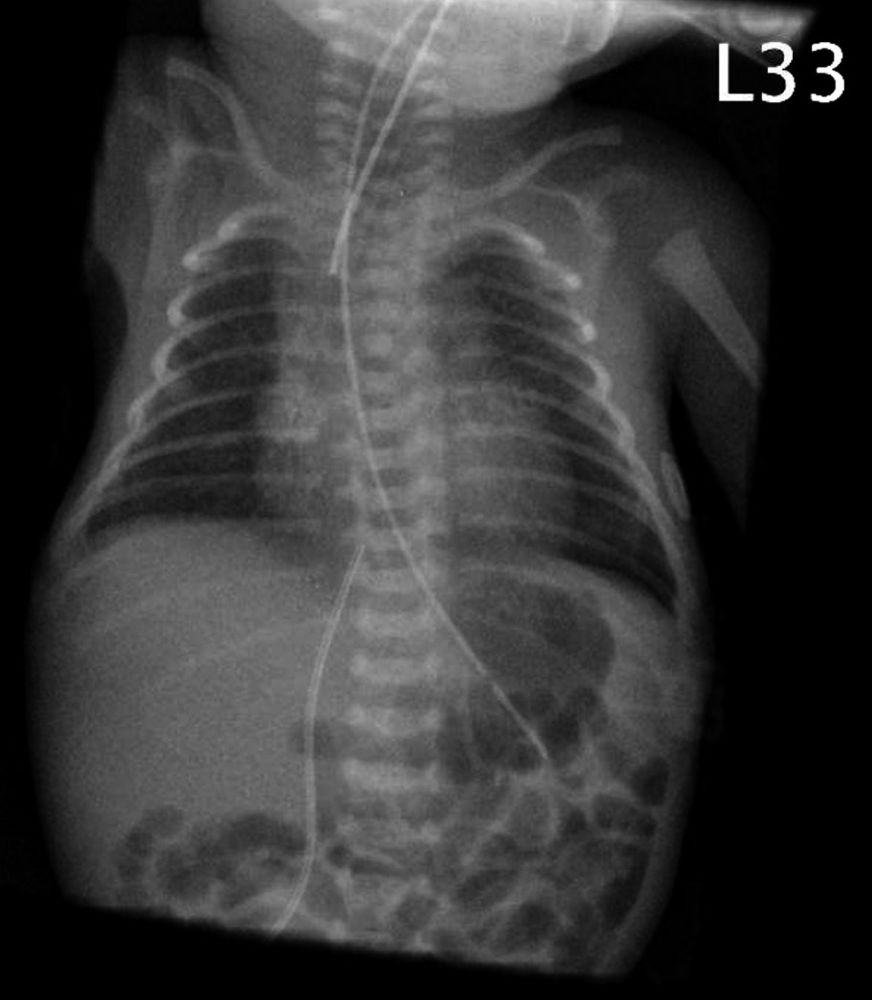

Laura 2. Lebenstag; Abbildung 1: Röntgen-Thorax: pulmonal Residuen des Atemnotsyndroms, einliegender Nabelvenenkatheter, Trachealtubus, Magensonde.

Ein weibliches Frühgeborenes, zyanotisch ohne Eigenatmung und muskelhypoton wird geboren. Auf der Erstversorgungseinheit erfolgt: Absaugen, Legen eines Nasopharyngealtubus und darüber nicht-invasive Beatmung ohne Besserung der Oxygenierung bei kaum auskultierbarem Atemgeräusch. Tubuslage und Kopfposition werden optimiert sowie Beatmungsdruck und -frequenz und sukzessive die Sauerstoffzufuhr erhöht – ohne Verbesserung. Daraufhin erfolgt die nasotracheale Intubation in der vierten Lebensminute und tracheale Gabe von Surfactant mit kurzzeitiger Besserung unter konventioneller Beatmung. Dann erneut ansteigender Sauerstoffbedarf. Auch die zweite Gabe Surfactant führt nicht zum Abfall des Sauerstoffbedarfs (maximal 90 Prozent; FiO2 0,9). Ein peripherer Venenzugang und ein Nabelvenenkatheter werden angelegt.

Folgende Befunde wurden erhoben: Apgar 3/6/7 nach 1/5/10 min; Nabelschnurarterien-pH (NS-pH) 7,36, Base excess (BE) -4,7; Gewicht 900 g (34. Perzentile), Länge 37,5 cm (66. Perzentile), Kopfumfang 25 cm (34. Perzentile). Das Frühgeborene wurde auf die Neugeborenenintensivpflegestation (NIPS) verlegt.

Bei anhaltend schwerer Oxygenierungsstörung und zunehmender Hyperkapnie erfolgt die Umstellung von konventioneller Beatmung auf Hochfrequenzoszillationsbeatmung (HFO; Oszillationsfrequenz 600/min). Darunter bessere Ventilation mit Abfall des pCO2, rückläufiger Sauerstoffbedarf auf FiO2 0,3. Bei der Hochfrequenzoszillationsbeatmung werden mit sehr hoher Frequenz (typischerweise 10 Hz = 600/min) Atemzugvolumina erzeugt, die keine alveoläre Ventilation im üblichen Sinne ermöglichen. Eine exakte physikalische Erklärung, wie bei dieser Beatmungsform das CO2 pulmonal eliminiert wird, gibt es nicht. Vorteil sind reduzierte Scherkräfte für die Lunge bei effektiver CO2-Auswaschung und ein stabiler Beatmungsmitteldruck zur Verbesserung der Oxygenierung.